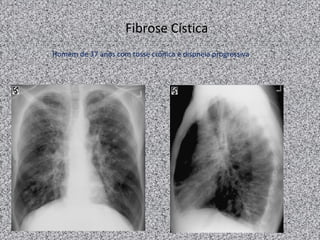

Fibrose Cística

Homem de 37 anos com tosse crônica e dispneia progressiva

Fibrose cística: imagem

Radiografia de tórax:

Normal;

Achados não específicos:

Aumento da trama broncovascular nos lobos

superiores;

Hiperinsuflação pulmonar;

Espessamento brônquico

Pneumotórax é complicação comum: até 20% dos

pacientes adultos

TACR de tórax:

Bronquiectasias (principal achado):

Pode ser dos 3 tipos; geralmente bilaterais;

Predomina nos lobos superiores;

Espessamento brônquico;

Impactação mucoide pode ocorrer;

Nódulos centrolobulares;

Árvore em brotamento;

Consolidações;

Lesões císticas ou bolhosas nos ápices;

Linfonodomegalias hilar e mediastinal

Anormalidades pleurais (derrame e/ou espessamento)